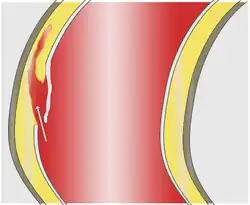

La dissection aortique est une affection rare et grave caractérisée par l'irruption de sang à l'intérieur de la paroi de l'aorte. Elle constitue une déchirure ou porte d'entrée, par laquelle le sang sous pression entre et décolle les feuillets superposés qui constituent la paroi élastique de l'aorte. La dissection de ces feuillets peut s'étendre sur une longue portion de l'aorte ascendante, la crosse aortique et/ou l'aorte descendante. Elle constitue une urgence chirurgicale.

La dissection débute par une « porte d'entrée », rupture de la paroi interne (intima) permettant le décollement de cette dernière en pleine media (partie moyenne de la paroi). Ce décollement s'étend le plus souvent d'amont en aval et forme une poche de sang circulant, le « faux chenal », séparé du « vrai chenal » (la lumière de l'artère) par un flap (constitué par la paroi décollée). Plus rarement, la progression se fait en rétrograde : d'aval en amont (un tiers des cas[11]). La porte d'entrée peut être multiple dans un quart des cas[12].